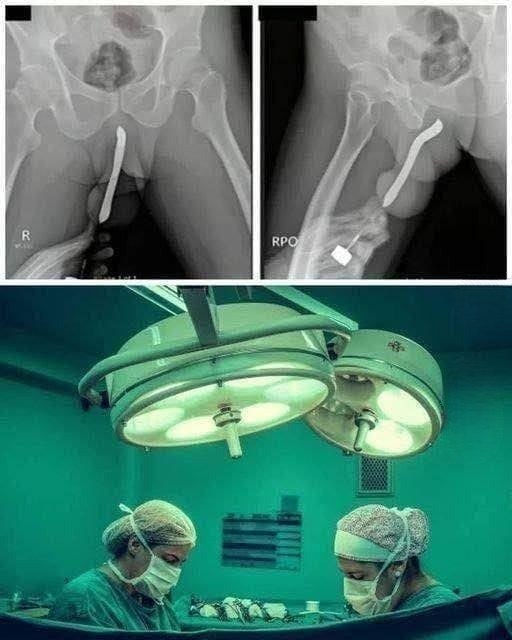

Medical professionals around the world often face situations that require not only skill but also calm decision-making under extreme pressure. Hospitals regularly treat broken bones, infections, and other common conditions, yet sometimes doctors encounter cases so unusual that they quickly capture public attention. The image you shared appears to depict such a situation—an X-ray revealing a foreign object inside a patient’s body and a surgical team preparing to address the problem in an operating room.

Although unusual cases like this may seem shocking at first glance, they highlight the importance of modern medical science, quick intervention, and the dedication of healthcare workers who work tirelessly to protect patient safety.

This article explores what situations like this may involve, how doctors diagnose and treat internal foreign objects, and why medical teams must act quickly when such emergencies occur.